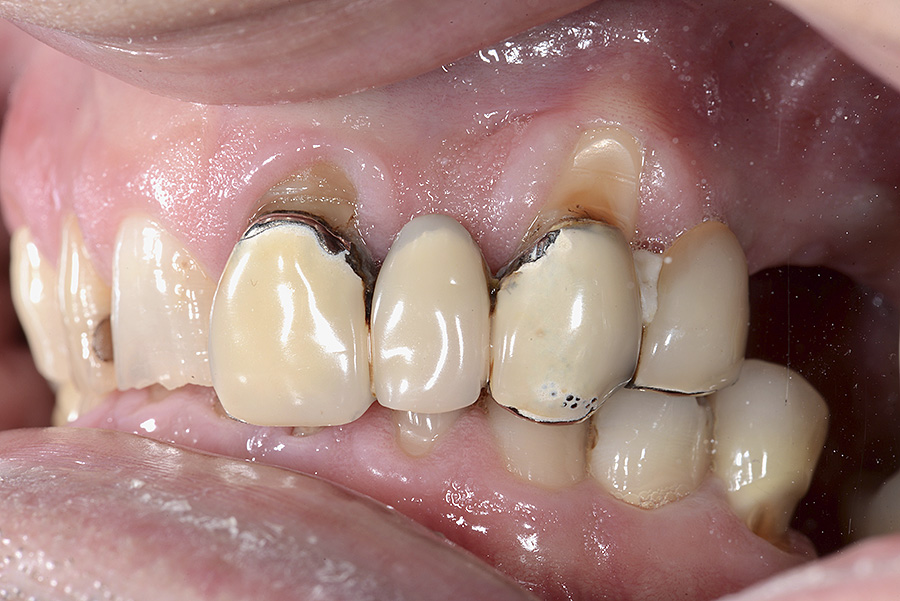

PREMESSA: in seguito all’estrazione dell’incisivo laterale superiore di destra, resasi necessaria per cause batteriche, si decide di affrontare il caso con il posizionamento di un impianto in sostituzione dell’elemento mancante dopo guarigione del sito infetto. Con tecniche rigenerative sia dei tessuti ossei mancanti a causa dell’infezione pregressa, sia dei tessuti gengivali che appaiono inizialmente troppo spostati in alto, si ripristina una corretta morfologia delle parabole (contorni) gengivali e delle papille interdentali (triangoli di gengiva tra due denti vicini).